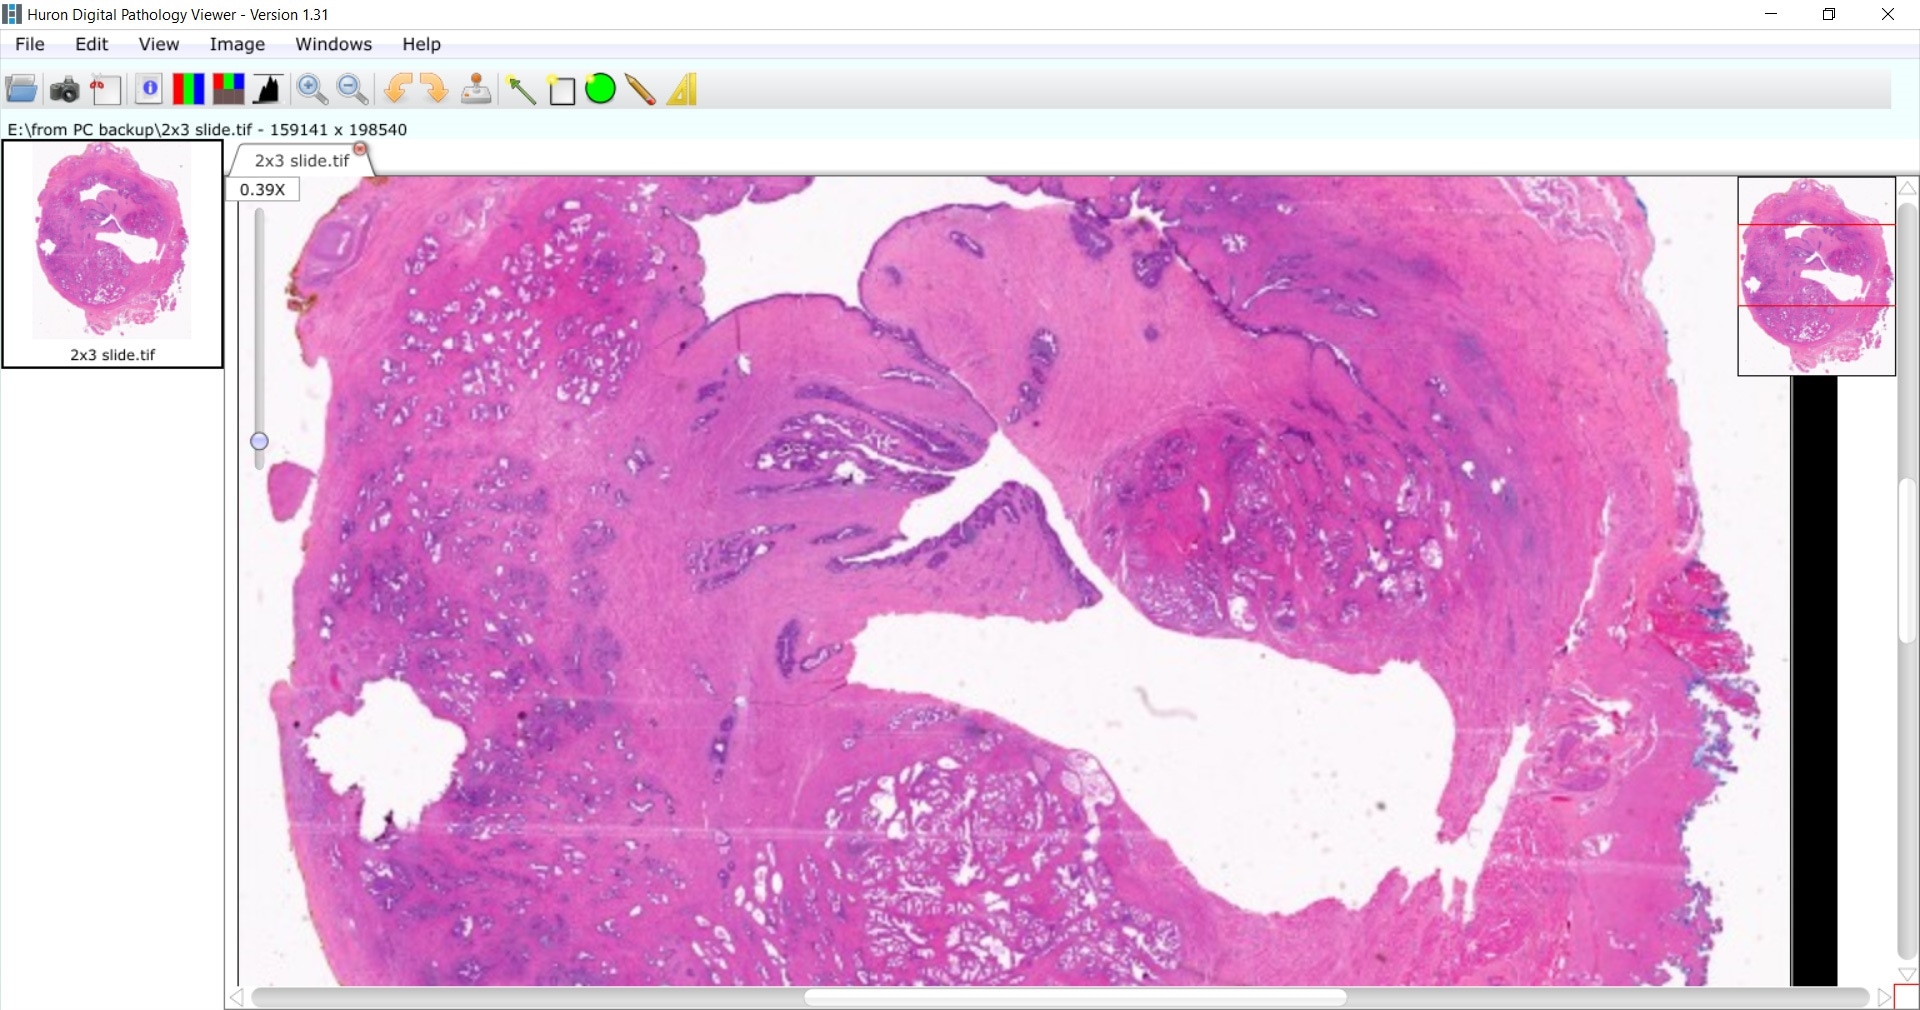

Image credit: Huron Digital Pathology.

In our institute, we perform full-mount processing of prostate slides. When a patient has a biopsy, they are processed in the standard way to produce a standard slide. For the full mounts, we take the whole prostate. We ink it, fix it and then then obtain many sections of the whole tissue.

We put those into a large cassette that is processed, and paraffin blocks are made. From those paraffin blocks we make very thin, unstained slides which are then stained with H&E. One of the challenges that is unique to scanning such large slides is the need for special equipment. You need special scanners; not every whole slide imaging scanner can accommodate these large slides.

The TissueScope scanner is optimized for whole mount slides, but it can also accommodate standard-sized slides as well. We like it because we are required to place whole mount tissue in special 2 by 3 slides and this scanner enables us to do that.

It enables us to mix and match to use standard slides, full mounts and it is even capable of scanning a slide up to 6 by 8, which is a very unique feature of the system. We can accommodate a large, high-throughput scanning workflow, all whilst maintaining good image quality. It is a very versatile, easy-to-use system that can scan a standard slide in less than a minute.